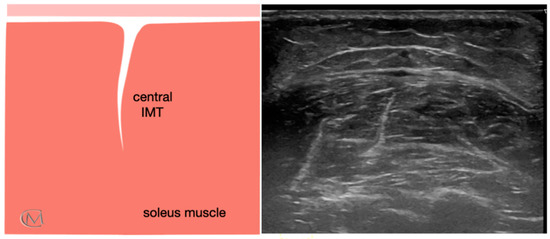

Echotexture features of the soleus muscle were reviewed for 84 subjects. They were divided based on the muscle echogenicity in three groups: Injury Type 1 group, healthy group (Figure 1), Injury Type 1 and Injury Type 2 (Figure 2). As in previous studies [7,24], a central IMT tear in the soleus muscle was identified when patients reported having symptoms for at least six months, and they established a self-rated progressive stiffness value greater than or equal to 4 points during sports exercises or during the soleus stretching, measured using the numeric rating scale (NRS) [25]. The enrollment was carried out in a private clinic specialized in sports injuries. First of all, researchers filled out the clinical history of the subjects. The presence of a central IMT injury of the soleus muscle was determined according to the following criteria: clinical history of the individuals, clinical evaluation performed by an experienced therapist and US examination carried out by an US-imaging specialist clinician with more than 15 years of experience.

Figure 2.

Ultrasound image of soleus muscle in athletes with injured soleus muscle. (A) Injury Type 1 group, shows an injured central IMT characterized by hypoechoic imagen; and (B) Injury Type 2 group, shows an injured central IMT characterized by fibrotic imagen; Left panel: anatomic diagram of soleus muscle; Middle panel: ultrasound image with marked lesion area (yellow line); Right panel: ultrasound image of the soleus muscle.

The main finding of the present study was to provide a better understanding and new insights about different injured soleus types located in the IMT by ultrasound parameters. In this study, an echotexture classification of injuries affecting the IMT of the soleus muscle is proposed, based on findings in the sports population. The classification may be useful in the clinical setting for the diagnosis, follow up and prevention of musculoskeletal injuries. Specifically, the results show that EV could be a muscle biomarker in athletes with soleus pathology. According to the echogenic pattern, the classification of soleus tears that authors propose is: Injury Type 1, identified by a hypoechoic area and characterized by a higher EV; and Injury Type 2, identified by a fibrotic area and characterized by a lower EV. The echogenic pattern of healthy people should be an intermediate value between both injured soleus types. An intra and inter-rater reliability test was carried out with the objective to increase the reliability of the scores of the assessments. They showed a high reliability in all parameters for this population.

The results described in this research are in line with previous studies that hypothesize the possibility to obtain a muscle biomarker with ultrasonography. In fact, the EV had been analyzed in different muscles of patients with amyotrophic lateral [19] and athletes with chronic lumbopelvic pain [21]. To the best of our knowledge, there are limited studies about the relationship between EV and different classifications of muscle injuries in sport field. Previously, De-la-Cruz-Torres et al. [7] compared the EV of patients with IMT injury of soleus muscle and healthy people, but they found no differences. Authors suggest that this could be because it is needed to determine the injury status to determine its echogenic pattern. Pathologies with the same symptomatology and lesional mechanism may be characterized by a different histology and, therefore, the diagnosis and treatment may be different. Authors hypothesize that IMT tears of the soleus muscle can be considered (Figure 2, Table 3): on the one hand, a re-injury characterized by a hypoechoic image, compatible with edema, and a higher EV (Injury type 1); and on the other hand, a fibrotic injury characterized by a fibrotic image, compatible with fibrosis, and a lower EV (Injury type 2). In this line, future studies are also needed to better explain the characteristics of the pathological features on injured muscle. Knowledge of basic anatomic and histology in combination with pathology imaging are required.